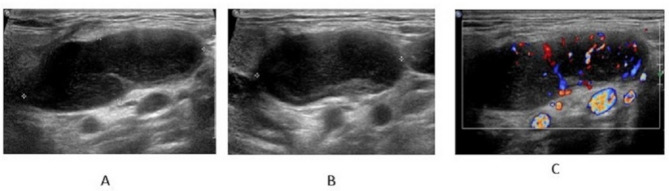

Results: A total of 41 patients were enrolled in the study, comprising 29 with HV-type, 4 with PC-type, and 8 with a mixed type. All patients presented with enlarged lymph nodes (LNs) characterized by a solitary mass, well-defined margins, and increased cortical thickness. Among these, 95.12% (39/41) exhibited an indistinct corticomedullary interface. Additionally, 41.46% (17/41) showed eccentric or asymmetrical cortical thickening, while 58.54% (24/41) demonstrated complete effacement of the fatty hilum. Approximately 24.39% (10/41) of cases exhibited macrocalcification, and 56.10% (23/41) displayed short linear hyperechoic foci within the lymph nodes. Furthermore, patients with HV-type and mixed-type conditions exhibited more abundant blood flow signals compared to those with PC-type (75.86% vs. 25% vs. 87.50%, P = 0.018).

Conclusions: Ultrasound characteristics of UCD generally comprise sizable, solitary masses with clearly delineated borders, a thickened cortex, and disappearance of the fatty hilum. Principal imaging indicators encompass microcalcifications and short linear hyper-echoes. Ultrasound represents an effective and non-invasive modality for the early identification and diagnosis of UCD.